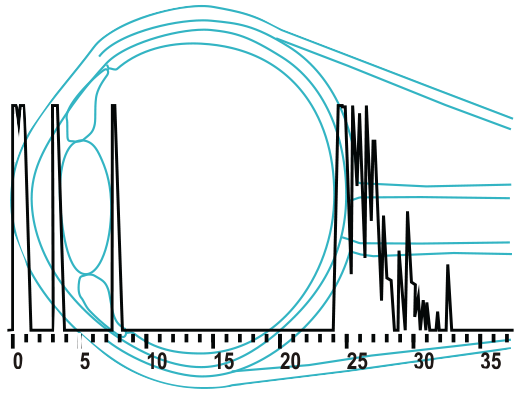

B-Scan

- Exceptional signal to noise ratio yields a deep penetration while maintaining high resolution image.

- 10 MHz transducer and 55 degrees of viewing angle with 256 scan lines produces a high quality sonogram.